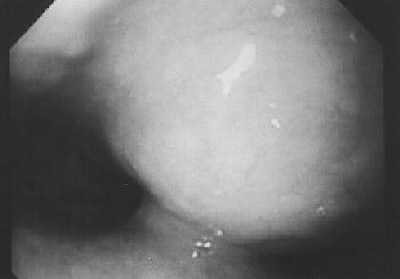

![]() |

| Fifty-year-old woman with submucosal tuberculous abscess in esophagus. Endoscopic image shows smooth-surfaced extraluminal mass of distal esophagus protruding into lumen with overlying mucosa intact. Lee KH, Kim HJ, Kim KH, Kim HG, "Esophageal Tuberculosis Manifesting as Submucosal Abscess," (AJR 2003; 180: 1482-1483). |

| Fifty-year-old woman with submucosal tuberculous abscess in esophagus. Esophageal endosonogram shows relatively well-demarcated heterogeneously hypoechoic mass (M) containing scattered echogenic debris in esophageal wall. Surrounding adventitia (arrowheads) appears somewhat irregular. Note small hypoechoic periesophageal lymph node (arrows) external relative to esophagus. L = fluid-filled esophageal lumen, P = center of probe, A = descending thoracic aorta. |

Line scan diffusion-weighted MR images, as well as contrast-enhanced CT and esophageal endosonogram, can be used for diagnosis and evaluation of esophageal tuberculosis, which is relatively rare and found in less than 1% of patients who die of TB (AJR, May 2003, Vol. 180:5, pp. 1482-1483).